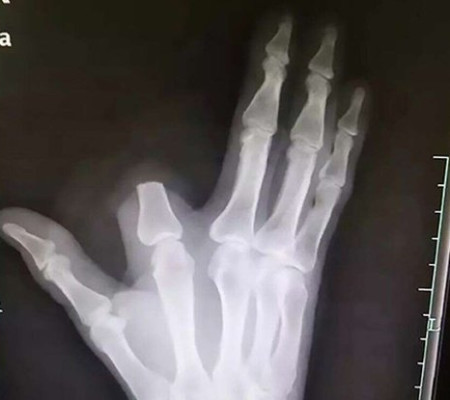

Raio-x sem o dedo | Foto: (Weibo / via South China Morning Post)

Portanto, para impedir que o veneno se espalhe, o homem de 60 anos agiu rapidamente, cortando o local da picada da cobra. Em seguida, embrulhou o dedo em um pano e fez a viagem de 80 quilômetros a um hospital em Hangzhou para receber tratamento.